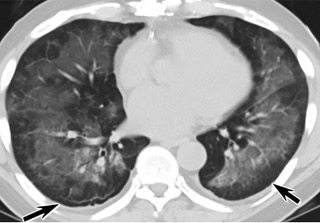

疑點(diǎn)一,電子煙患者的CT影像和臨床表現(xiàn)并不具有特異性。所謂美國(guó)電子肺炎患者,其實(shí)是對(duì)沒(méi)有其他合理診斷證據(jù)、吸食電子煙肺炎患者的統(tǒng)稱。這些患者在病發(fā)前90天內(nèi)吸食了電子煙,尤其值得注意的是,部分患者的CT影像特征和臨床表現(xiàn)與病毒性肺炎患者極其相似。

中、下肺軸位CT平掃顯示毛玻璃樣混濁伴胸膜下保留(箭頭)。(同一病人CT影像)